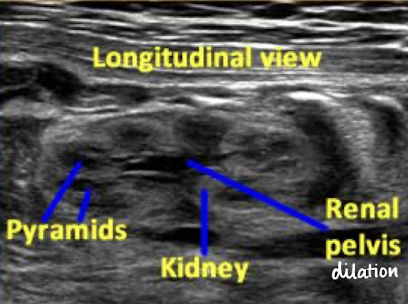

what plane was this taken in?

longitudinal

SONO: kidneys

homogeneous cortex

hypoechoic pyramids

anechoic collecting system